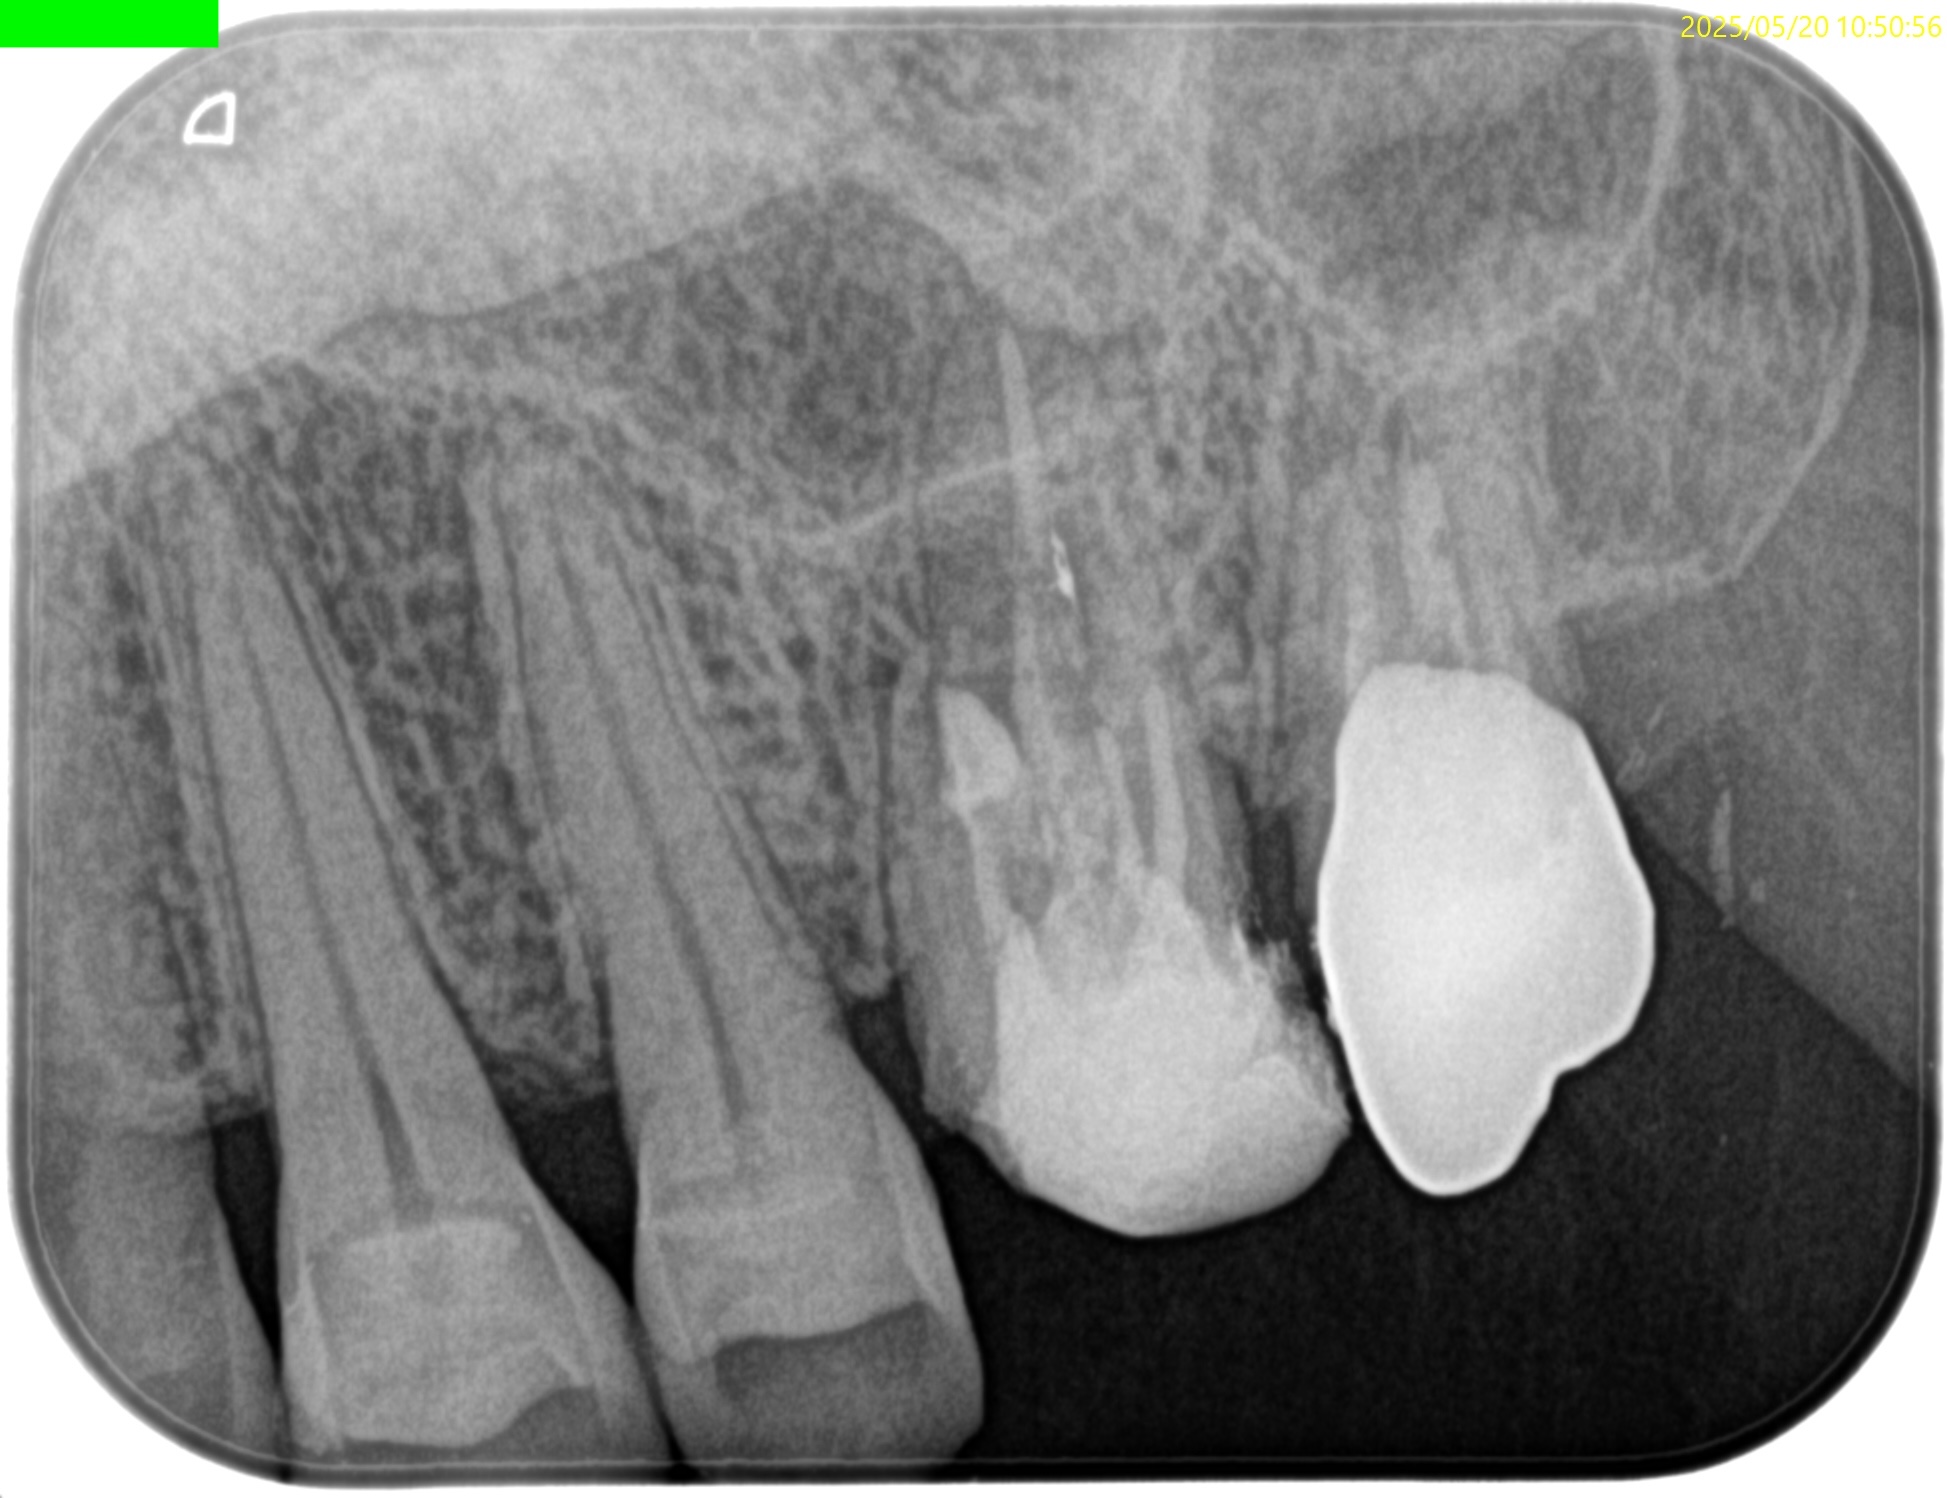

Pre-op Endo test(2025.4.14)

MB

MB2は確実に存在するが石灰化が進み穿通できるか?わからない。

また、Sinus tractが根尖孔外細菌感染の可能性もある。

このことから再根管治療よりも外科治療の方に軍配が上がるだろう。

DB

P

Pulp Dx: Previously treated

Periapical Dx: Chronic apical abscess

Recommended Tx: Apicoectomy